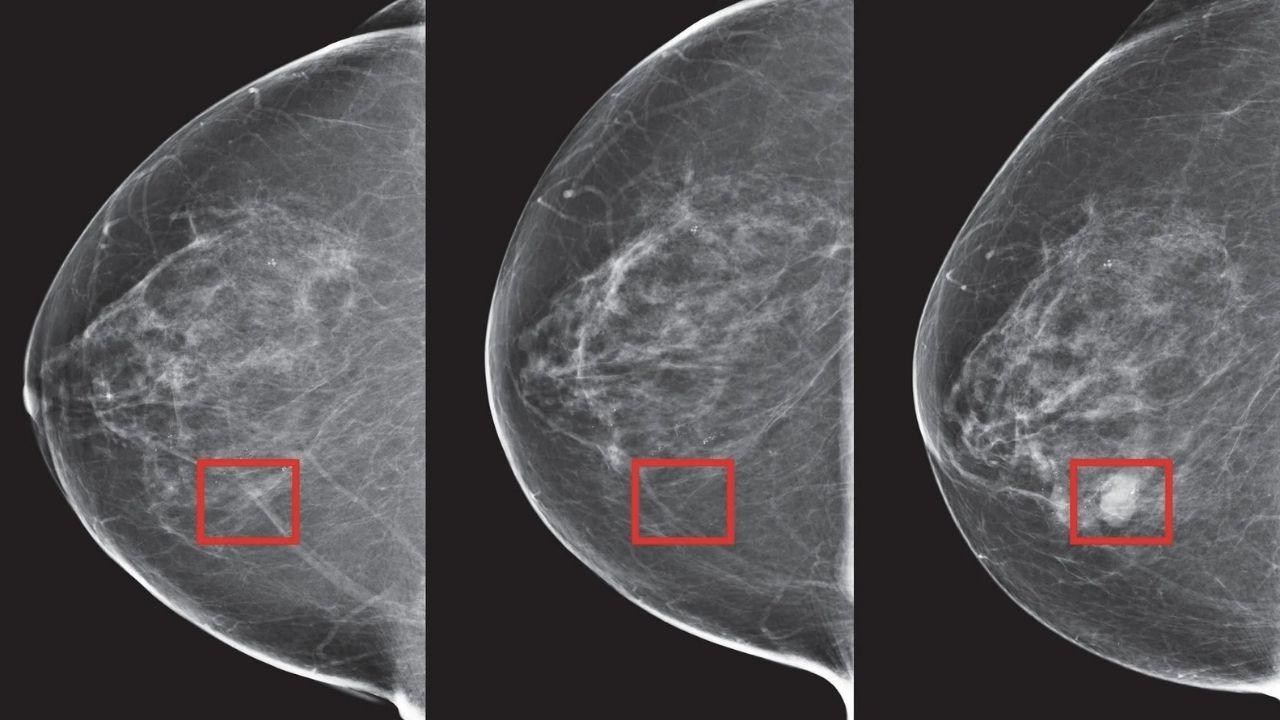

Despite medical advancements, India struggles with high breast cancer mortality due to late detection and low awareness. Early screening is crucial, and AI is transforming diagnostics by improving accuracy as well as efficiency. AI-powered screening tools such as AI-integrated mammography machines can aid radiologists in recognising patterns and spotting malignancies that might be missed by human observation, facilitating well-informed decisions and faster interventions. For this, the AI models have to be trained with huge datasets generated through mammography images. The need for faster, better diagnoses in India is urgent; the number of radiologists is low, which means AI tools could potentially enhance diagnosis speed and enable timely treatment.